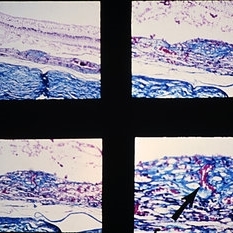

Slide 9-94

Slide 9-94

Feb 26 2019 by Lancaster Course in Ophthalmology

Macular disciform lesion in the ocular histoplasmosis syndrome. Note choroidal scar with vessels (arrow) extending through a break in Bruch's membrane.

Condition/keywords: Bruch's membrane, disciform macular lesion, ocular histoplasmosis syndrome (OHS)

Slide 9-66

Slide 9-66

Feb 26 2019 by Lancaster Course in Ophthalmology

Midperipheral punched-out lesions in the presumed ocular histoplasmosis syndrome. There is scarring in the choroid and retina, discontinuity in Bruch's membrane, and loss of the RPE. An infiltrate of lymphocytes is present in the subjacent choroid (lower middle and right).

Condition/keywords: Bruch's membrane, ocular histoplasmosis syndrome (OHS), retinal pigment epithelium, scar